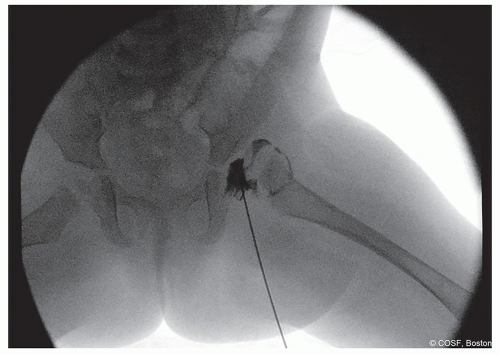

Figure 20-1 ▪ Arthrogram of subluxated left hip. (Courtesy of Children’s Orthopaedic Surgery Foundation.)

In dislocated hip, try to insert into the vacant acetabulum in the inferior side (Figure 20.1)

If you happen to not be in the joint, when you inject contrast material, it will decrease the chances that you create an aberrant “dust cloud” over your areas of interest

In subluxated/dysplastic hips, flex hip and aim for the proximal portion of the inferior femoral neck